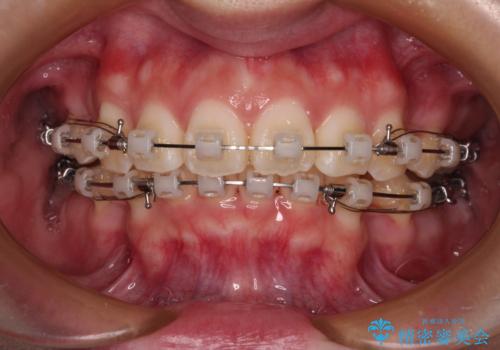

- 矯正装置

- クリアブラケット

- 前歯部のデコボコと口元が出ているのが気になるとのことで来院された患者様です。

口元の突出感の解消と、このままデコボコを解消するとさらに出っ歯傾向になってしまうことを考慮し、上下左右の小臼歯を抜歯しクリアブラケットにて矯正していくこととしました。